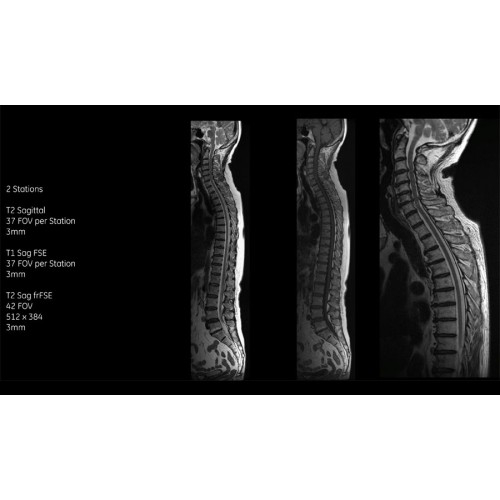

Благодаря революционному программному пакету Silent Suite уровень шума снижается до 77 дБ, что всего на 3 дБ выше уровня окружающей среды. Программный пакет Silent Suite теперь включает полный пакет приложений для исследования ЦНС (T1, T2 FLAIR, DWI10, МРА). Кроме того, мы расширили возможности визуализации Silent за пределы ЦНС для исследований скелетно-мышечной системы и позвоночника. Silent Suite – платформа, содержащая в себе все импульсные последовательности для бесшумного сканирования.